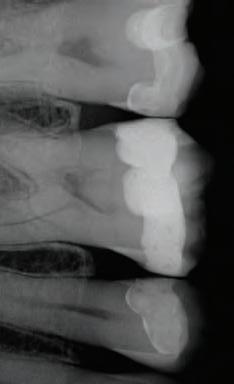

Other types of stains can penetrate into enamel and dentin from the inside, as a consequence of diseases, injury or medical treatment, e.g. congenital, systemic, metabolic, pharmacological, traumatic, or iatrogenic factors such as dental fluorosis, jaundice, tetracycline, and adult minocy-cline stains, porphyria, trauma, and erythroblastosis fetalis. To treat staining from these causes, a medical, in-office whitening system is needed. In many cases such focused whitening may make restorations, veneers or crowns unnecessary or postpone them for a long time.

Evaluate the origin of tooth staining and check for restorations that could affect the final result (use X-Ray if needed). Assess the intention of whitening system (cosmetic for generic “day-by-day” discoloration; medical devices for teeth discolored by disease, injury or medical treatment). Consider amending your periodical medical history by adding a question about the patient’s satisfaction with their oral esthetics. Explain to the patient that restorations will not whiten, and discuss the possible need for new restorations after whitening. Check existing sensitivities, and perform an adequate treatment before starting a whitening procedure. Pregnant or breastfeeding women should not whiten. Patients with serious health concerns should consult their primary care provider prior to treatment. Cosmetic teeth whitening treatments are not permited under the age of 18.

Determine origin of staining, evaluate gingival and dental health. Check for restorations in the esthetic zone that may not match after whitening. Discuss changing them out or resurfacing after whitening.